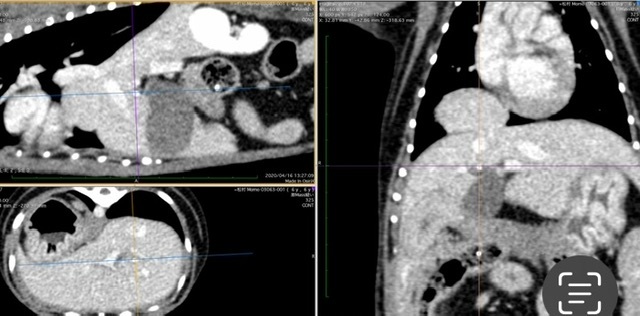

ももちゃんを悪質な繁殖屋から救ってもらったその1年後の健康診断(血液検査、エコー、レントゲン)で胆嚢に油が溜まる胆泥症が発覚し薬剤の投与を開始。レントゲンの肺の近くに腫瘍のようなものが見えると告げられ、その後すぐ地元の動物医療センターでCTを撮ってもらいました。結果、腫瘍ではなく『後大静脈孔ヘルニア(レアなケースだそうです)ではないか』との診断を受け、定期的にレントゲンと血液検査を行うようにいわれました。(最近4月23日に後大静脈孔ヘルニアの疑いは高くないということが分かり、病名は先天性胸膜腹膜ヘルニアと最終診断されました)

これまで3か月に一回の定期的なレントゲンと血液検査をしてきましたが、2022年11月のレントゲン検査で2年で肝臓が胸部側へ2倍移行していることが分かり、手術を勧められました。

肝臓の一部が横隔膜を突き抜けている様子。

しかし、今年4月東京へ渡航し、動物医療センター(循環器科・脳神経科)での専門的な検査(CT・MRI)を2日間に渡り行った結果、MRI検査では「脊髄空洞症」と「てんかん」両方あること、その他にも多発性ヘルニア(腰椎、頚椎、他)が発覚し、痙攣の方はてんかんによるものと診断を受けました。 胆泥症・てんかん・脊髄空洞症に関してはこれ以上悪くならないように定期的な検診や毎月の通院、一生涯毎日の薬剤投与となりました。

4月東京の動物医療センターにてCT。血液検査の結果。

そしてMRI検査の前日CT検査の結果から、『先天性胸膜腹膜ヘルニア』の診断が下されました。